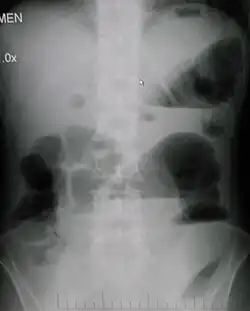

| Upright abdominal X-ray demonstrating a small bowel obstruction. Note multiple air fluid levels. | |

Causes of bowel obstruction include adhesions, hernias, volvulus, endometriosis, inflammatory bowel disease, appendicitis, tumors, diverticulitis, ischemic bowel, tuberculosis and intussusception.[1][2] Small bowel obstructions are most often due to adhesions and hernias while large bowel obstructions are most often due to tumors and volvulus.[1][2] The diagnosis may be made on plain X-rays; however, CT scan is more accurate.[1] Ultrasound or MRI may help in the diagnosis of children or pregnant women.[1]

Radiological signs of bowel obstruction include bowel distension (small bowel loops dilated >3 cm) and the presence of multiple (more than 2) air-fluid levels on supine and erect abdominal radiographs.[16] Ultrasounds may be as useful as CT scanning to make the diagnosis.[17]

Contrast enema or small bowel series or CT scan can be used to define the level of obstruction, whether the obstruction is partial or complete, and to help define the cause of the obstruction. The appearance of water-soluble contrast in the cecum on an abdominal radiograph within 24 hours of it being given by mouth predicts resolution of an adhesive small bowel obstruction with sensitivity of 97% and specificity of 96%.[18]